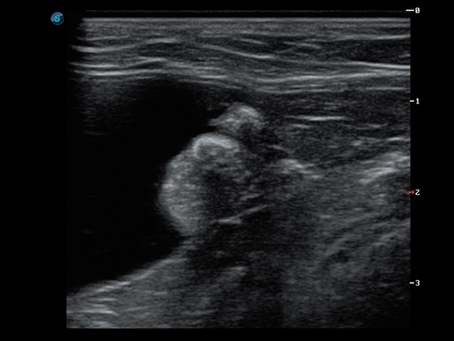

Colonic mast cell tumour in a cat

A cat was referred for an abdominal ultrasound following the palpation of a potential mass during a routine abdominal examination. The...